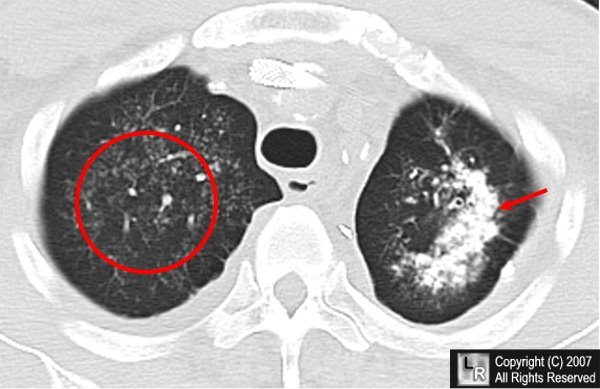

Ex: Coal workers Pneumoconiosis

Coal workers Pneumoconiosis

Macrophages lining the alveoli engulf coal dust and release cytokines that stimulate inflammation of the surrounding tissues

Include distortion of the lung architecture (scarring) and airflow obstruction

Lungs look black instead of pink- "Black lung disease”